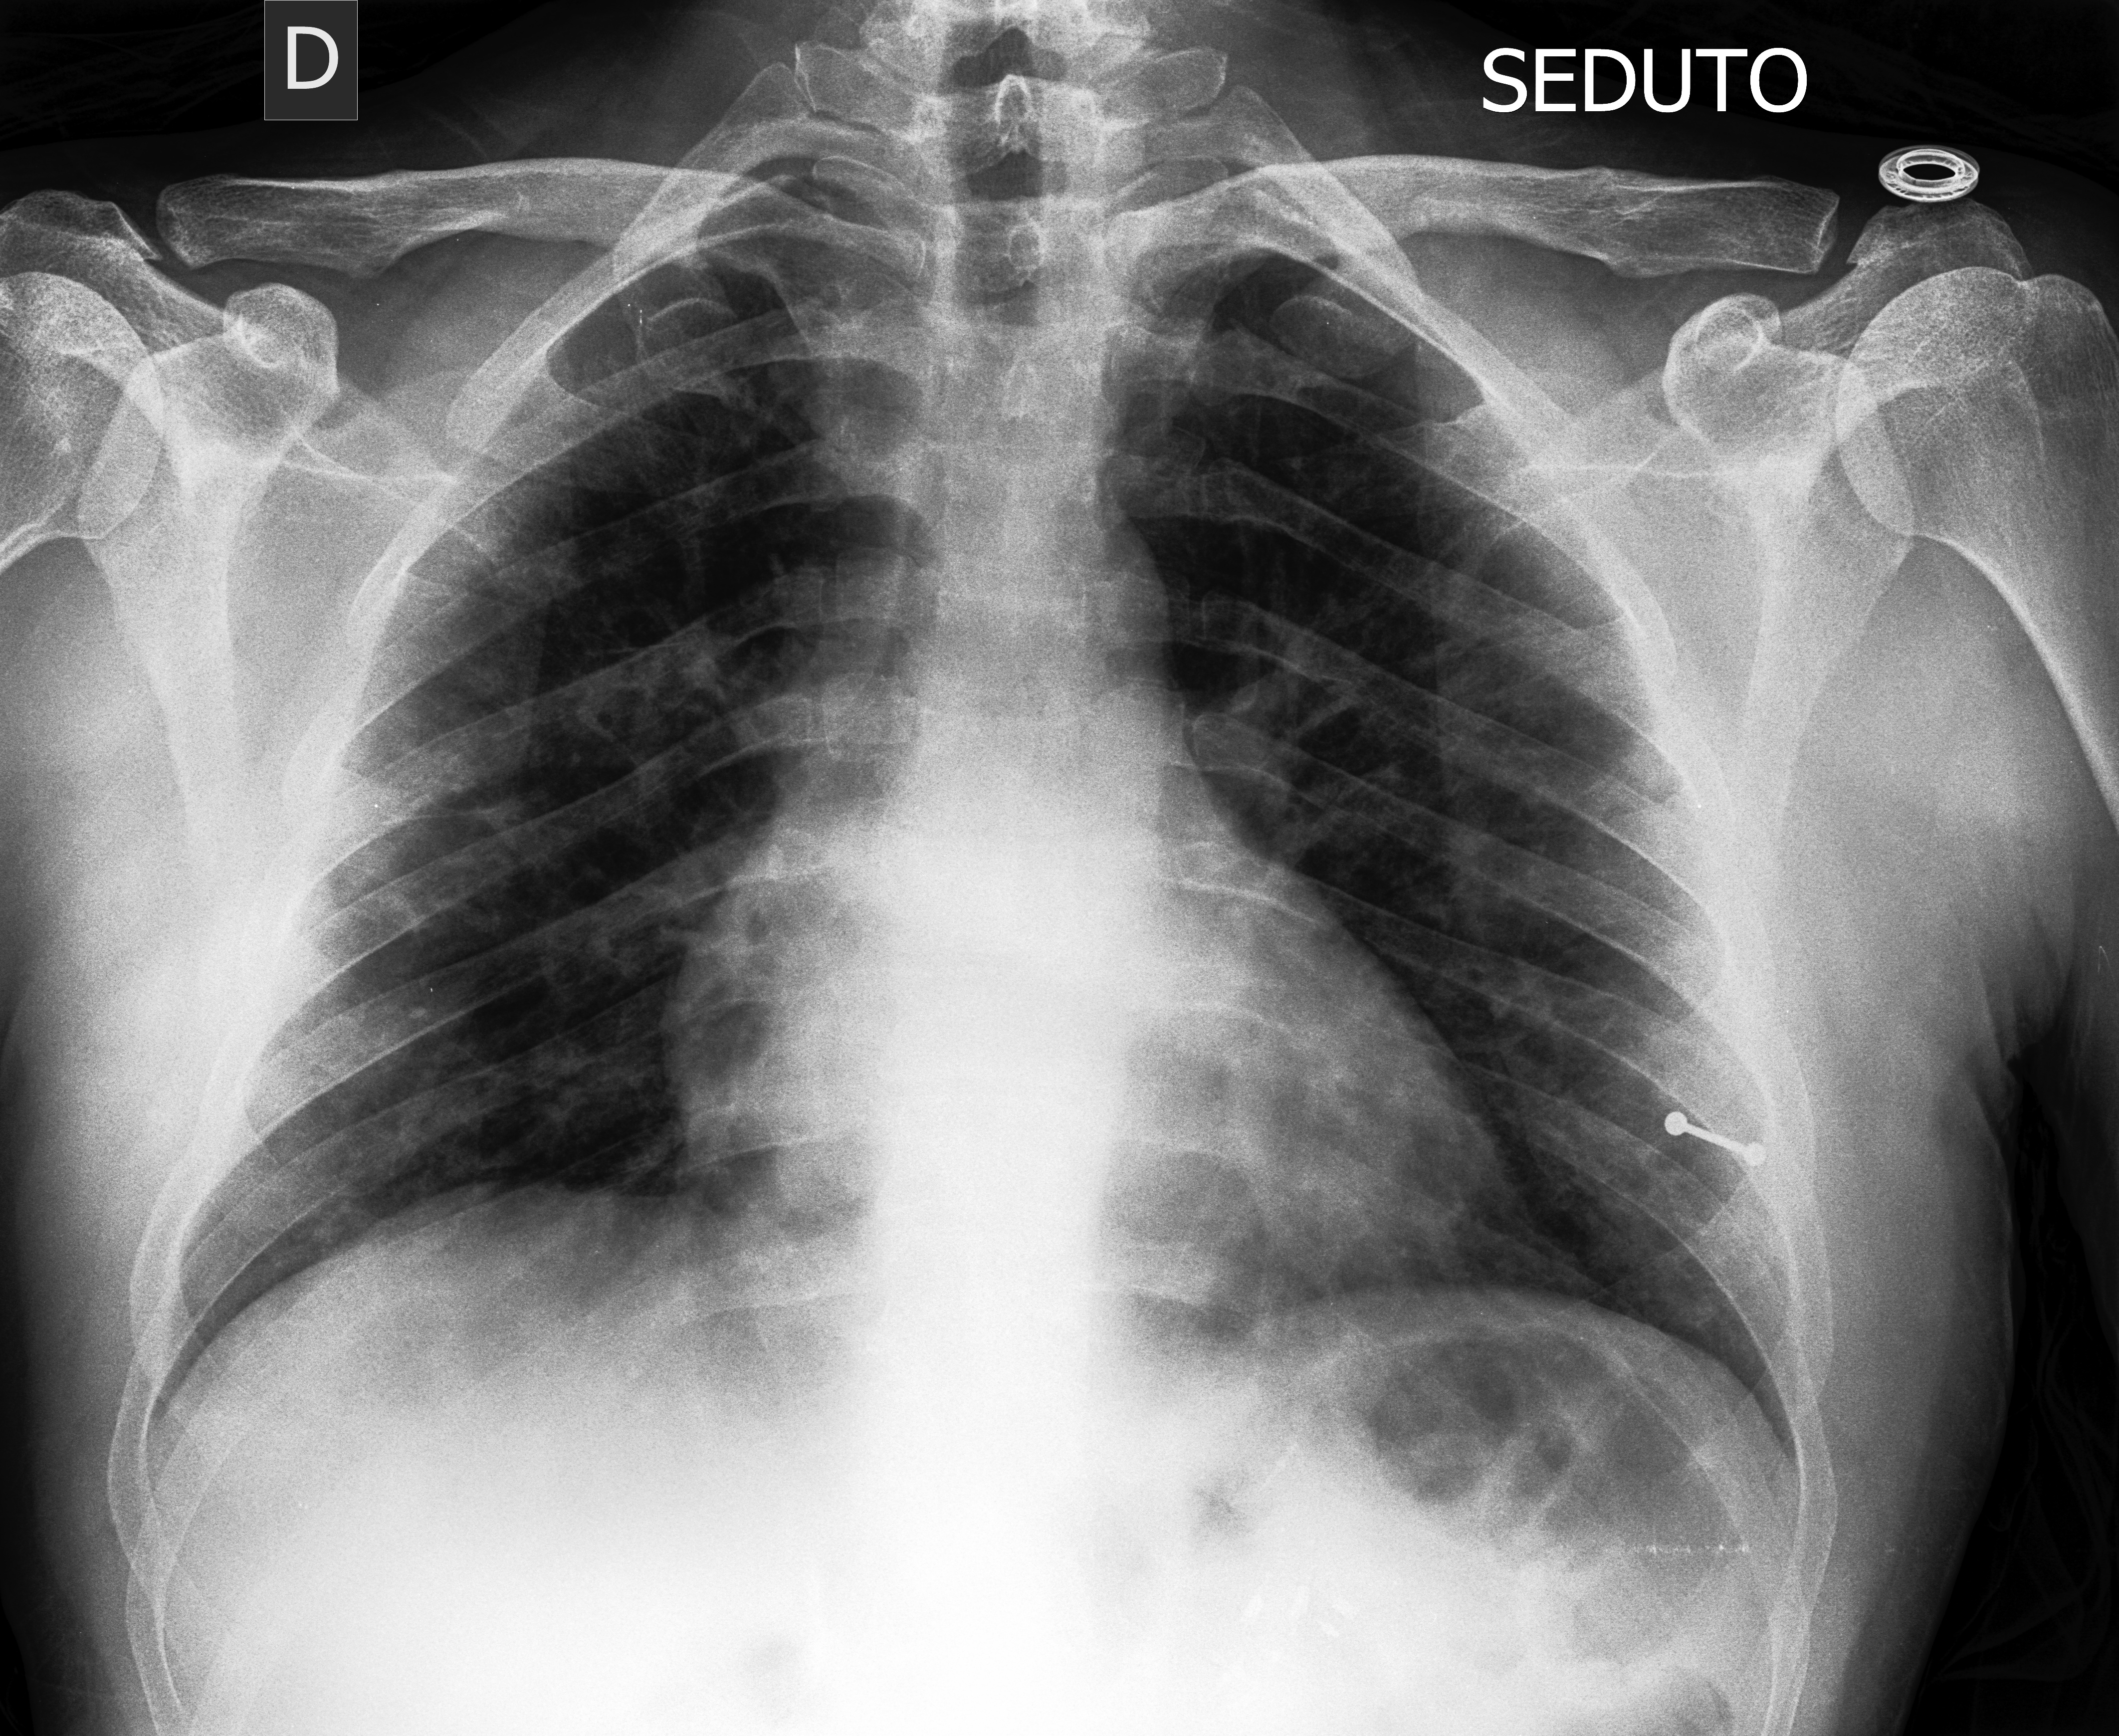

基于无监督/有监督对比学习,设计brain_tumor分类模型。